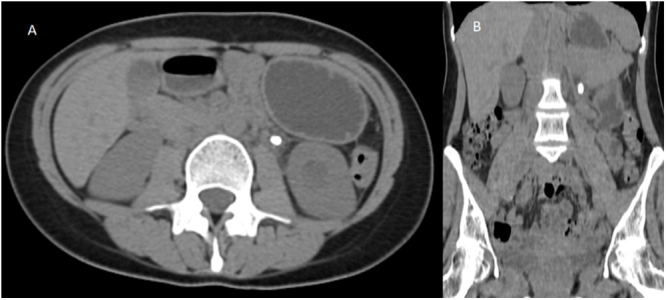

Case presentation: A 23-year-old female presented with acute left flank pain, imaging for which revealed a calculus in the left proximal ureter. A repeat imaging after a few weeks of medical management revealed a calculus of the same dimension at the lower pole calyx of the left kidney, with no calculus present at the initial site, indicating retrograde migration of the calculus. The patient subsequently underwent extracorporeal shockwave lithotripsy with complete stone clearance.